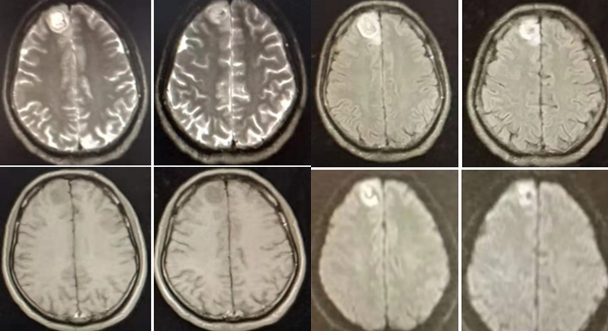

2018.11.3核磁如下:

2018.12.27核磁如下:

2019.1.19核磁如下:

答案:MELAS。其影像典型表现:CT:部分见基底节钙化。MRI:T2WI,FLAIR,DWI序列上相应的高信号;ADC可为高信号,低信号或混杂信号,提示细胞毒性水肿和血管源 性水肿同时存在;磁共振波谱(MRS)提示脑部乳酸的存在。病灶多分布在皮层和皮层下白质,深部皮层不受累;急性到亚急性时期病灶变化可有明显波动,迁移至完全消失;反复发作后脑萎缩。